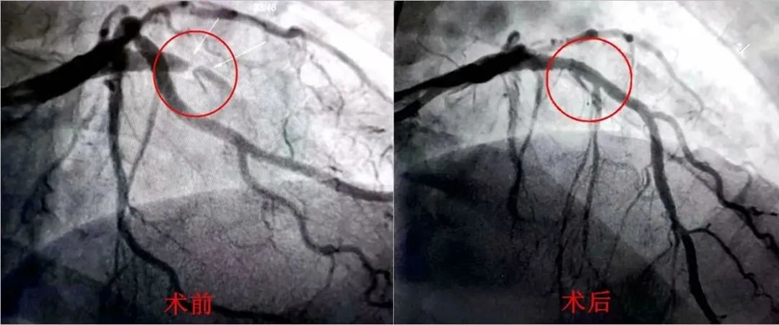

术中造影发现,李先生心脏前降支近段完全闭塞。赖仙辉带领救心团队第一时间植入心脏支架,开通生命通路,成功救下李先生一命。